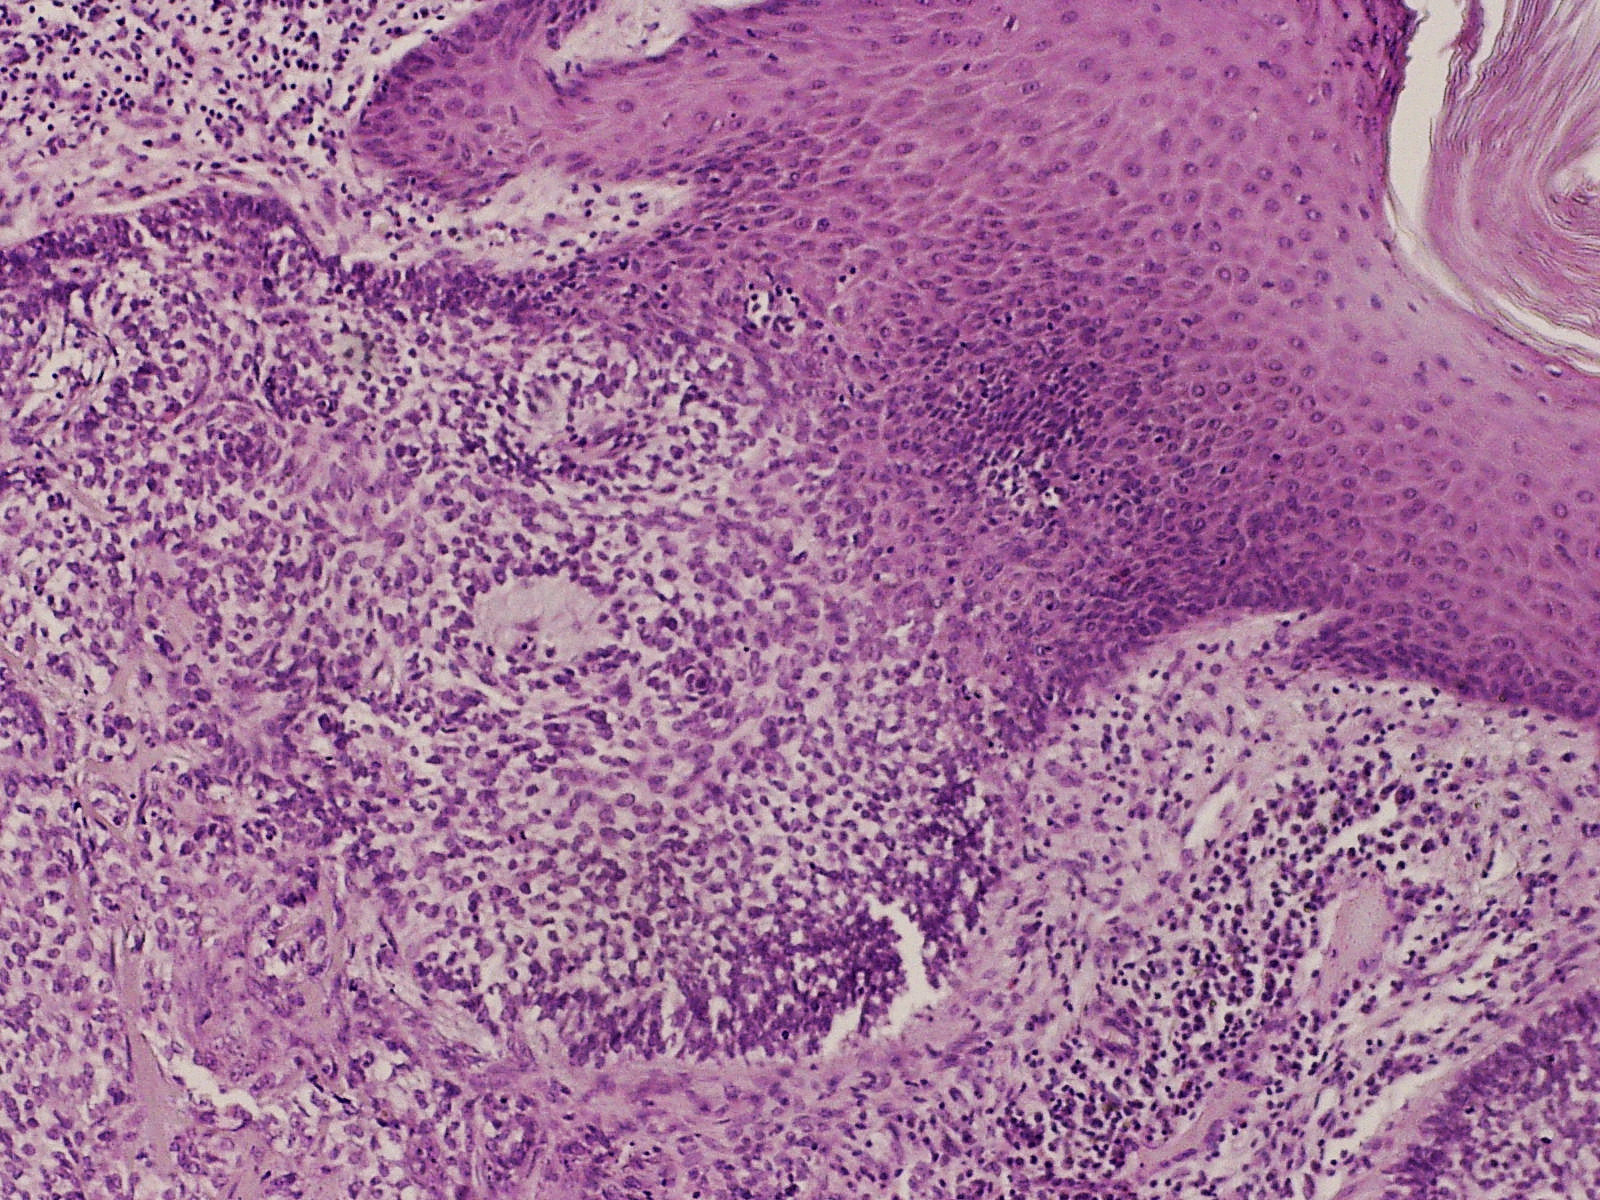

Een eccrien poroom (poroma eccrinum, eccrine poroma) is een benigne epitheliale tumor, uitgaande van de zweetklierafvoergang en kan dus gerangschikt worden onder de adnextumoren. De meest voorkomende vorm van een eccrien poroom is een solitaire tumor onder de voet. Histologisch kunnen buisstructuren worden aangetroffen, passend bij de origine (distale deel zweetklier afvoergang), en zweet secernerende eccriene cellen. Ook apocriene cellen kunnen voorkomen (apocrien poroma). Tumortjes uitgaande van de distale afvoergang worden ook wel acrospiroma genoemd. Eccrine poroma komt uit deze groep het meest voor. Het is niet bekend waardoor poroma ontstaat. Er is geen familiaire factor. Het kan in een naevus sebaceus ontstaan.

Hidroacanthoma simplex oftewel intraepidermaal poroma is een poroma met nestjes cuboide cellen met buisvormige differentiatie, beperkt tot de epidermis, zonder betrokkenheid van de dermis. Een dermal duct tumor (intradermal poroma) is een scherp begrensd poroma, geheel in de dermis liggend.

eccrien poroma eccrien poroma eccrien poroma (PA)

PA-Foto: L. Wozniak en K.W. Zielinski - Wikimedia (Creative Commons license 3.0).